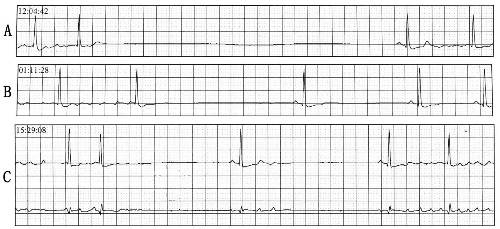

心动过缓-心动过速综合征,窦性心动过缓根蒂上继发房性心动过速窦性